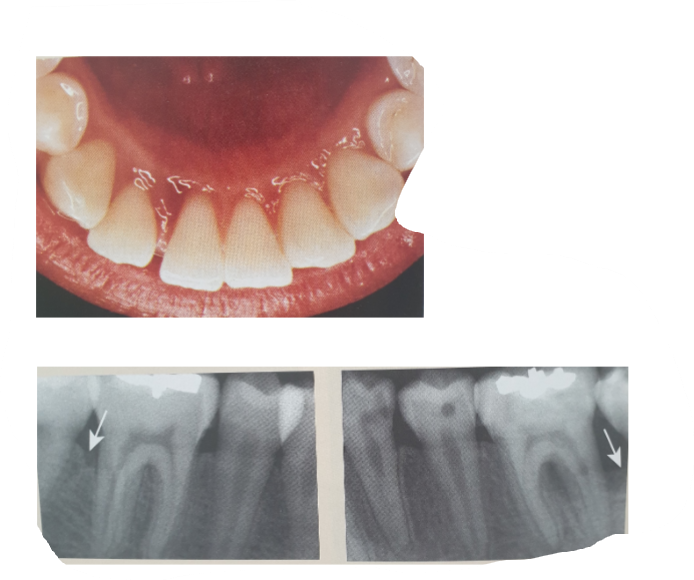

22

Q

What stage is this?

A

Stage 4

splain

tooth loss (if more than 5, and breakdown of dentition/occlusion= stage 4)

23

Stage 3

any where to right of staging= where we sit.

might be stage 1

but Stage 3 bc RBL + vertical bone loss

pockets (if we don’t have CAL then look at RBL) + 30% bone loss